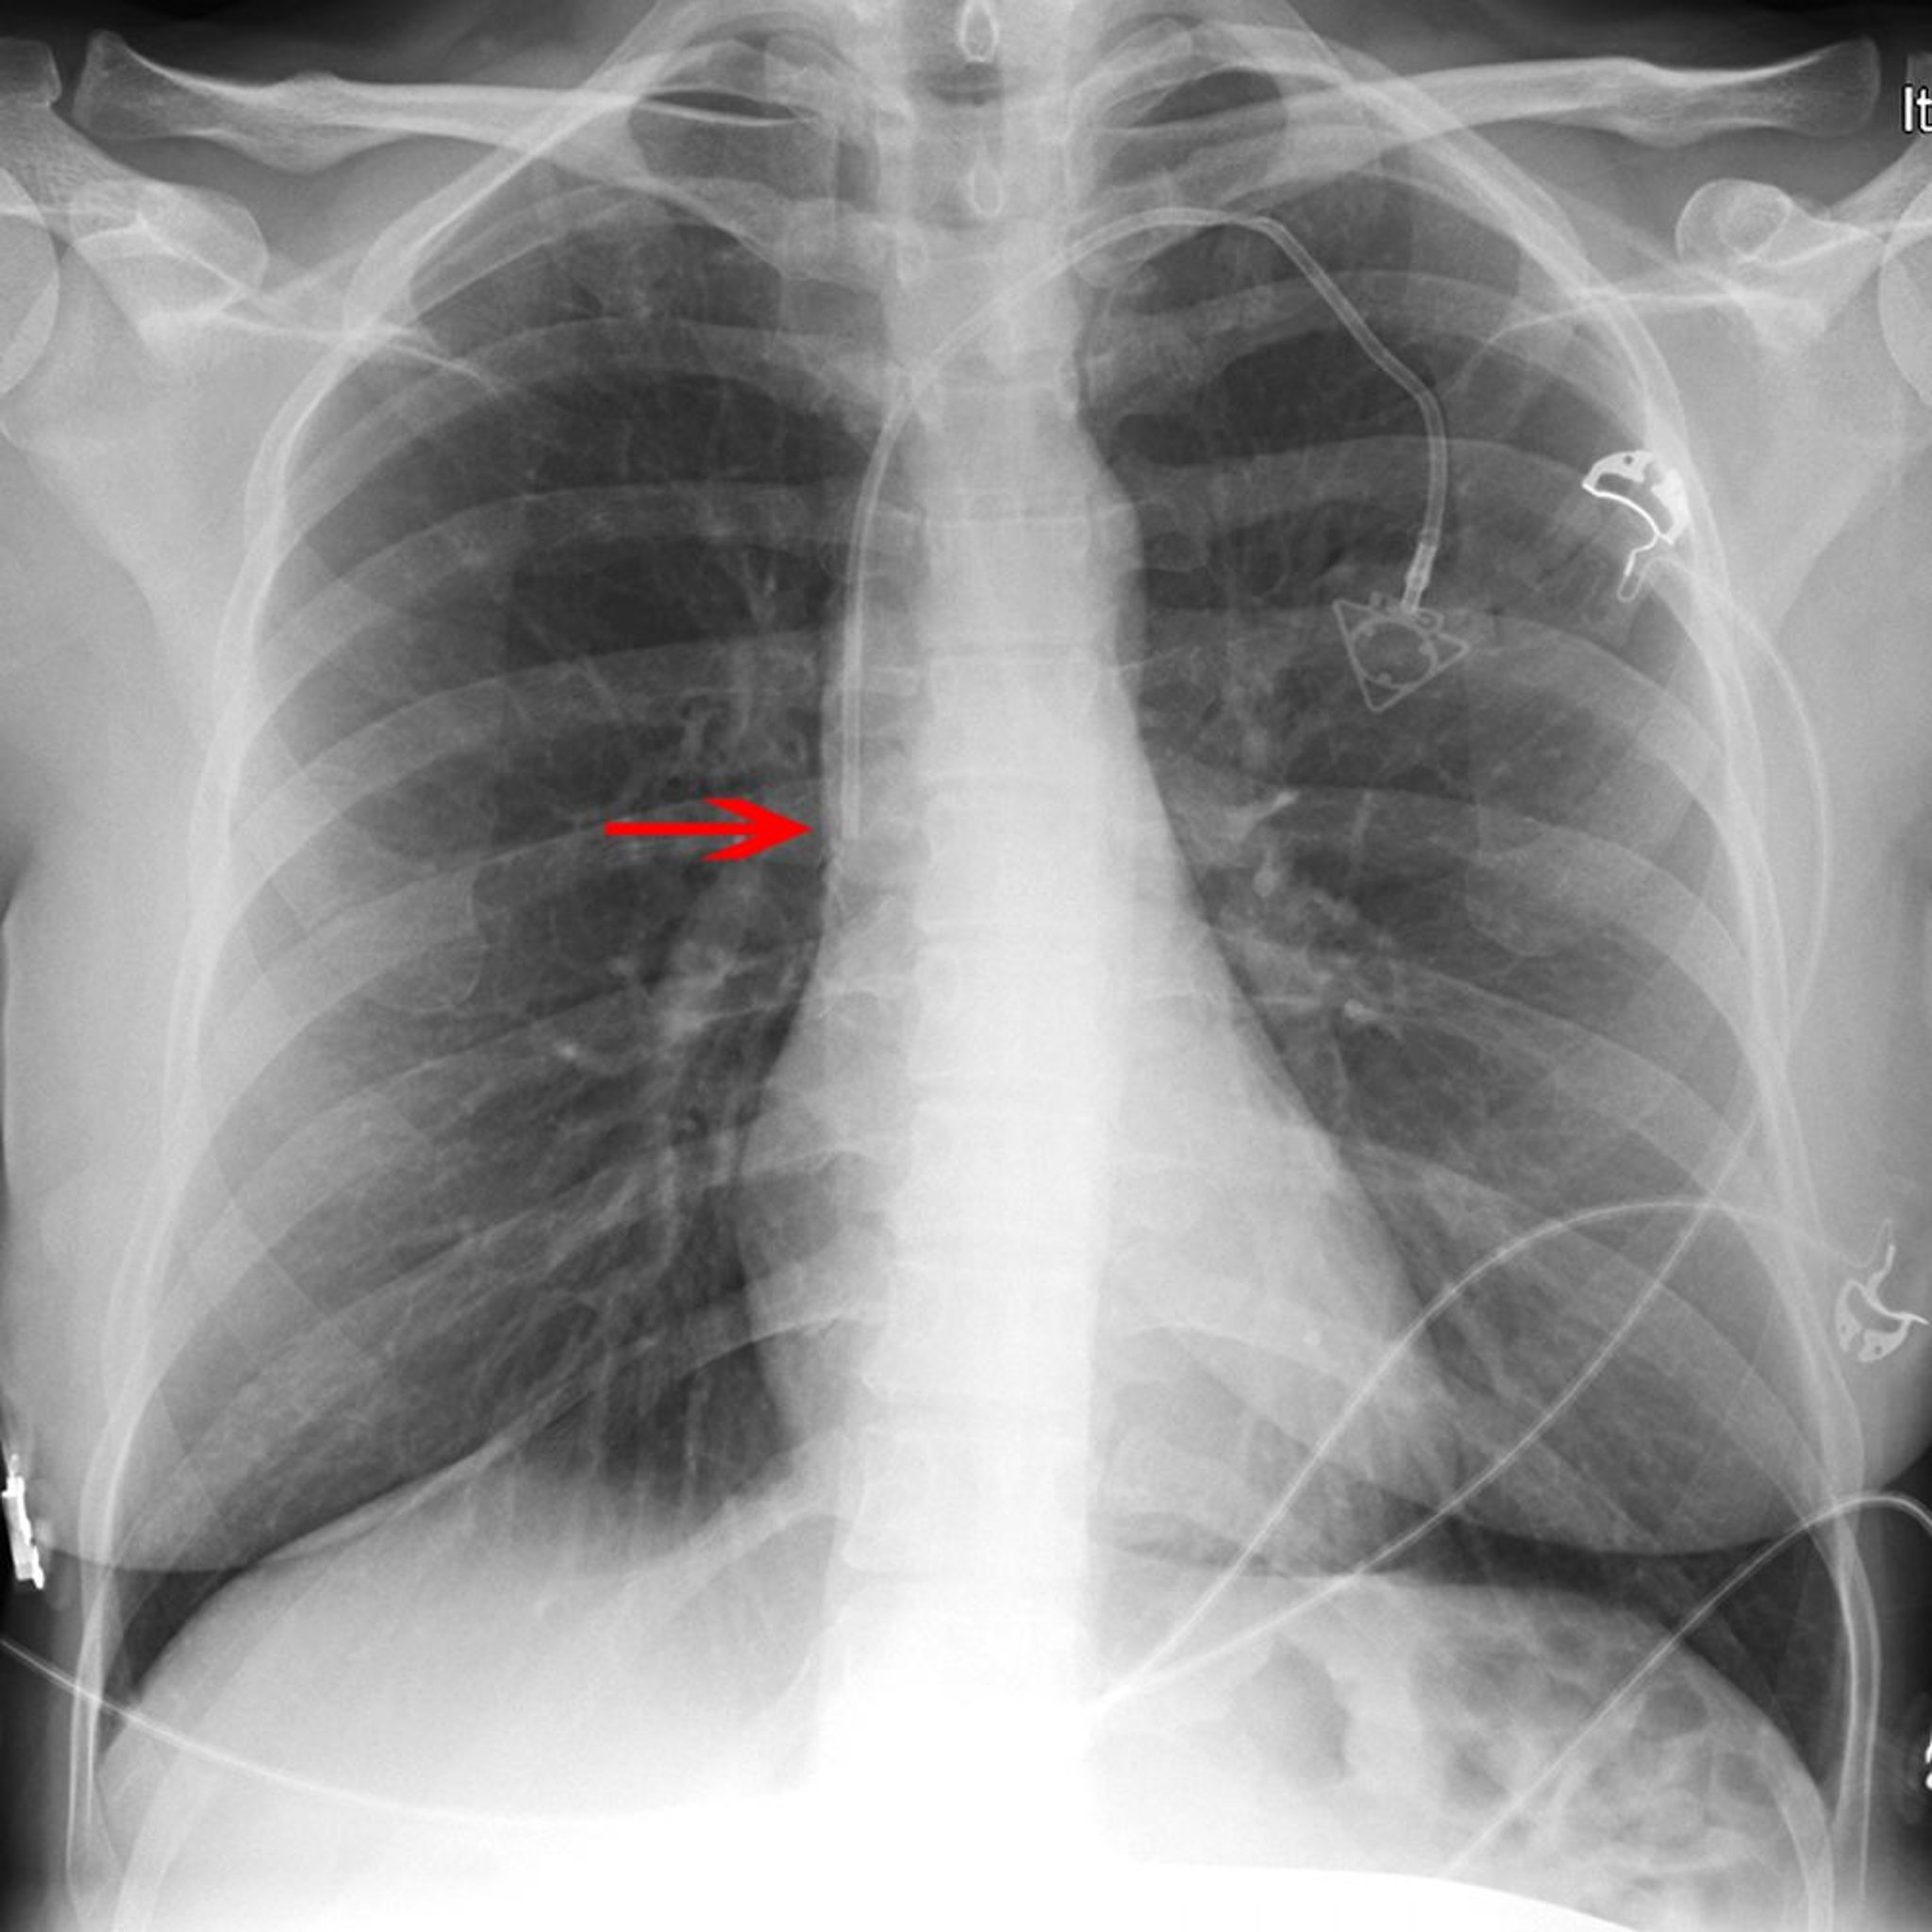

RX di un catetere venoso centrale

La freccia rossa indica la punta di un catetere venoso della succlavia sinistra (posizionato appropriatamente nella porzione inferiore della vena cava superiore).

© 2017 Elliot K. Fishman, MD.